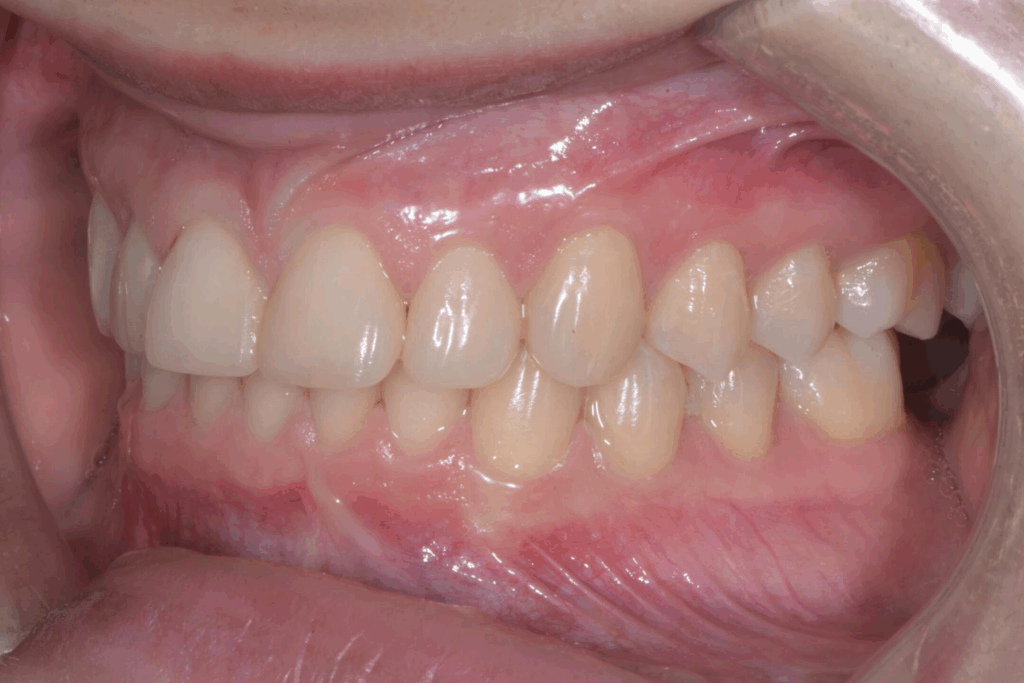

La prima fase del trattamento è stata un’analisi approfondita. Durante il check-up, abbiamo confermato la diagnosi di agenesia dei secondi molari permanenti inferiori, una condizione congenita che lascia spazi vuoti nell’arcata. Abbiamo inoltre rilevato che gli incisivi superiori erano di dimensioni ridotte rispetto al resto dei denti e che la paziente presentava un morso profondo, con gli incisivi superiori che coprivano eccessivamente quelli inferiori. Questa valutazione completa ci ha permesso di creare un piano di trattamento personalizzato e preciso, tenendo conto di tutte le problematiche presenti.

Per affrontare le sfide del caso, abbiamo optato per l’utilizzo di allineatori trasparenti. Questo tipo di trattamento è stato scelto per la sua efficacia nel muovere i denti in modo preciso e graduale, ma anche per la sua discrezione, fondamentale per una paziente in età scolare. Il piano di trattamento ha previsto una serie di allineatori personalizzati, che la paziente doveva sostituire con il passare delle settimane.

- Chiusura degli spazi: gli allineatori sono stati programmati per spostare i denti posteriori e chiudere gli spazi vuoti lasciati dall’agenesia dei settimi, evitando la necessità di impianti o ponti.

- Correzione della verticalità: il trattamento ha lavorato per estrusione e intrusione selettiva di alcuni denti, al fine di correggere il morso profondo e ristabilire una corretta occlusione.